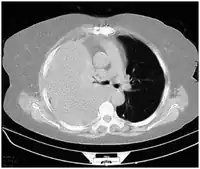

Diagnosis

Hemothoraces are most commonly detected using a chest X-ray, although ultrasound is sometimes used in an emergency setting.[22] It can be suspected in any person with any form of chest trauma.[6] However, plain X-rays may miss smaller hemothoraces while other imaging modalities such as computed tomography (CT), or magnetic resonance imaging may be more sensitive.[22] In cases where the nature of an effusion is in doubt, a sample of fluid can be aspirated and analysed in a procedure called thoracentesis.[8] Physical examination is used initially. Auscultation has been reported to have an accuracy of nearly 100% in diagnosing hemopneumothorax.[3]

Computed tomography (CT or CAT) scans may be useful for diagnosing retained hemothorax as this form of imaging can detect much smaller amounts of fluid than a plain chest X-ray. However, CT is less used as a primary means of diagnosis within the trauma setting, as these scans require a critically ill person to be transported to a scanner, are slower, and require the subject to remain supine.[23][26]